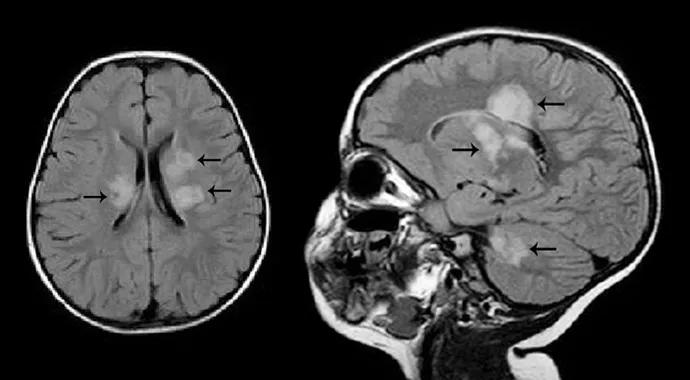

She had initially presented to another hospital for investigation of an acute onset of ataxia. Her brain MRI revealed extensive demyelinating white matter lesions involving bilateral corona radiata, white matter adjacent to the atria and right frontal horn, bilateral temporal lobes and the subcortical white matter (Figure 1).

Moodley-Fig1

Figure 1. MRI brain (January 2011). T2 FLAIR axial images with black arrows demonstrating (A) Bilateral white matter lesions in the cerebellum, and (B) bilateral white matter lesions in the periventricular regions.